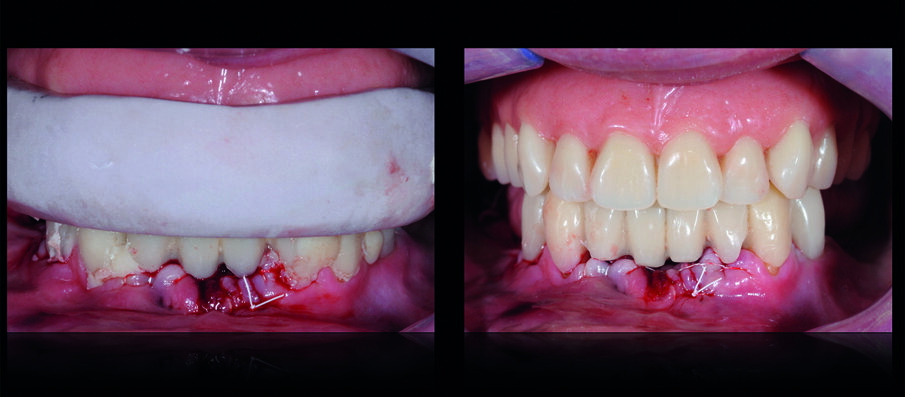

Dopo la loro rimozione e aspettato il periodo di guarigione, sono state rilevate le impronte iniziali e, dopo aver costruito un porta-impronte ed il suo successivo bordaggio funzionale, è stata rilevata l’impronta di precisione del mascellare superiore. Sul modello master, è stato realizzato un vallo in cera che ha permesso la registrazione dei rapporti inter-mascellari e il montaggio dei modelli in articolatore tramite arco facciale. Sono state così realizzate una protesi rimovibile provvisoria superiore e una protesi fissa inferiore. In una seduta successiva sono stati estratti gli elementi inferiori non recuperabili e la protesi fissa inferiore è stata ribasata e stabilizzata sui pilastri residui (Fig. 6). Sono stati successivamente valutati i parametri funzionali ed estetici comparandoli con la situazione iniziale (Fig. 7), osservando il miglioramento della qualità del supporto dei tessuti periorali (Fig. 8). La fase successiva ha previsto la terapia implantare: previa adeguata ceratura è stata realizzata una guida chirurgica che ha permesso il posizionamento ideale degli impianti dentali nell’arcata inferiore (Fig. 9).

Dopo la loro osteo-integrazione, gli impianti sono stati improntati e, dopo aver registrato la posizione di relazione centrica alla dimensione verticale già testata, è stata verificata la loro posizione utilizzando una placca in resina che ha permesso anche di confermare l’adeguatezza della dimensione verticale di occlusione. Gli ultimi due denti residui sono stati estratti ed è stata consegnata alla paziente una protesi provvisoria fissa inferiore, avvitata sugli impianti (Fig. 10). Nei 30 giorni successivi sono stati valutati funzione, occlusione, fonetica ed estetica e sono state trasferite tutte le informazioni delle protesi provvisorie in quelle definitive. La protesi superiore è stata duplicata e tale replica è stata utilizzata per eseguire l’impronta di precisione del mascellare edentulo (Fig. 11).